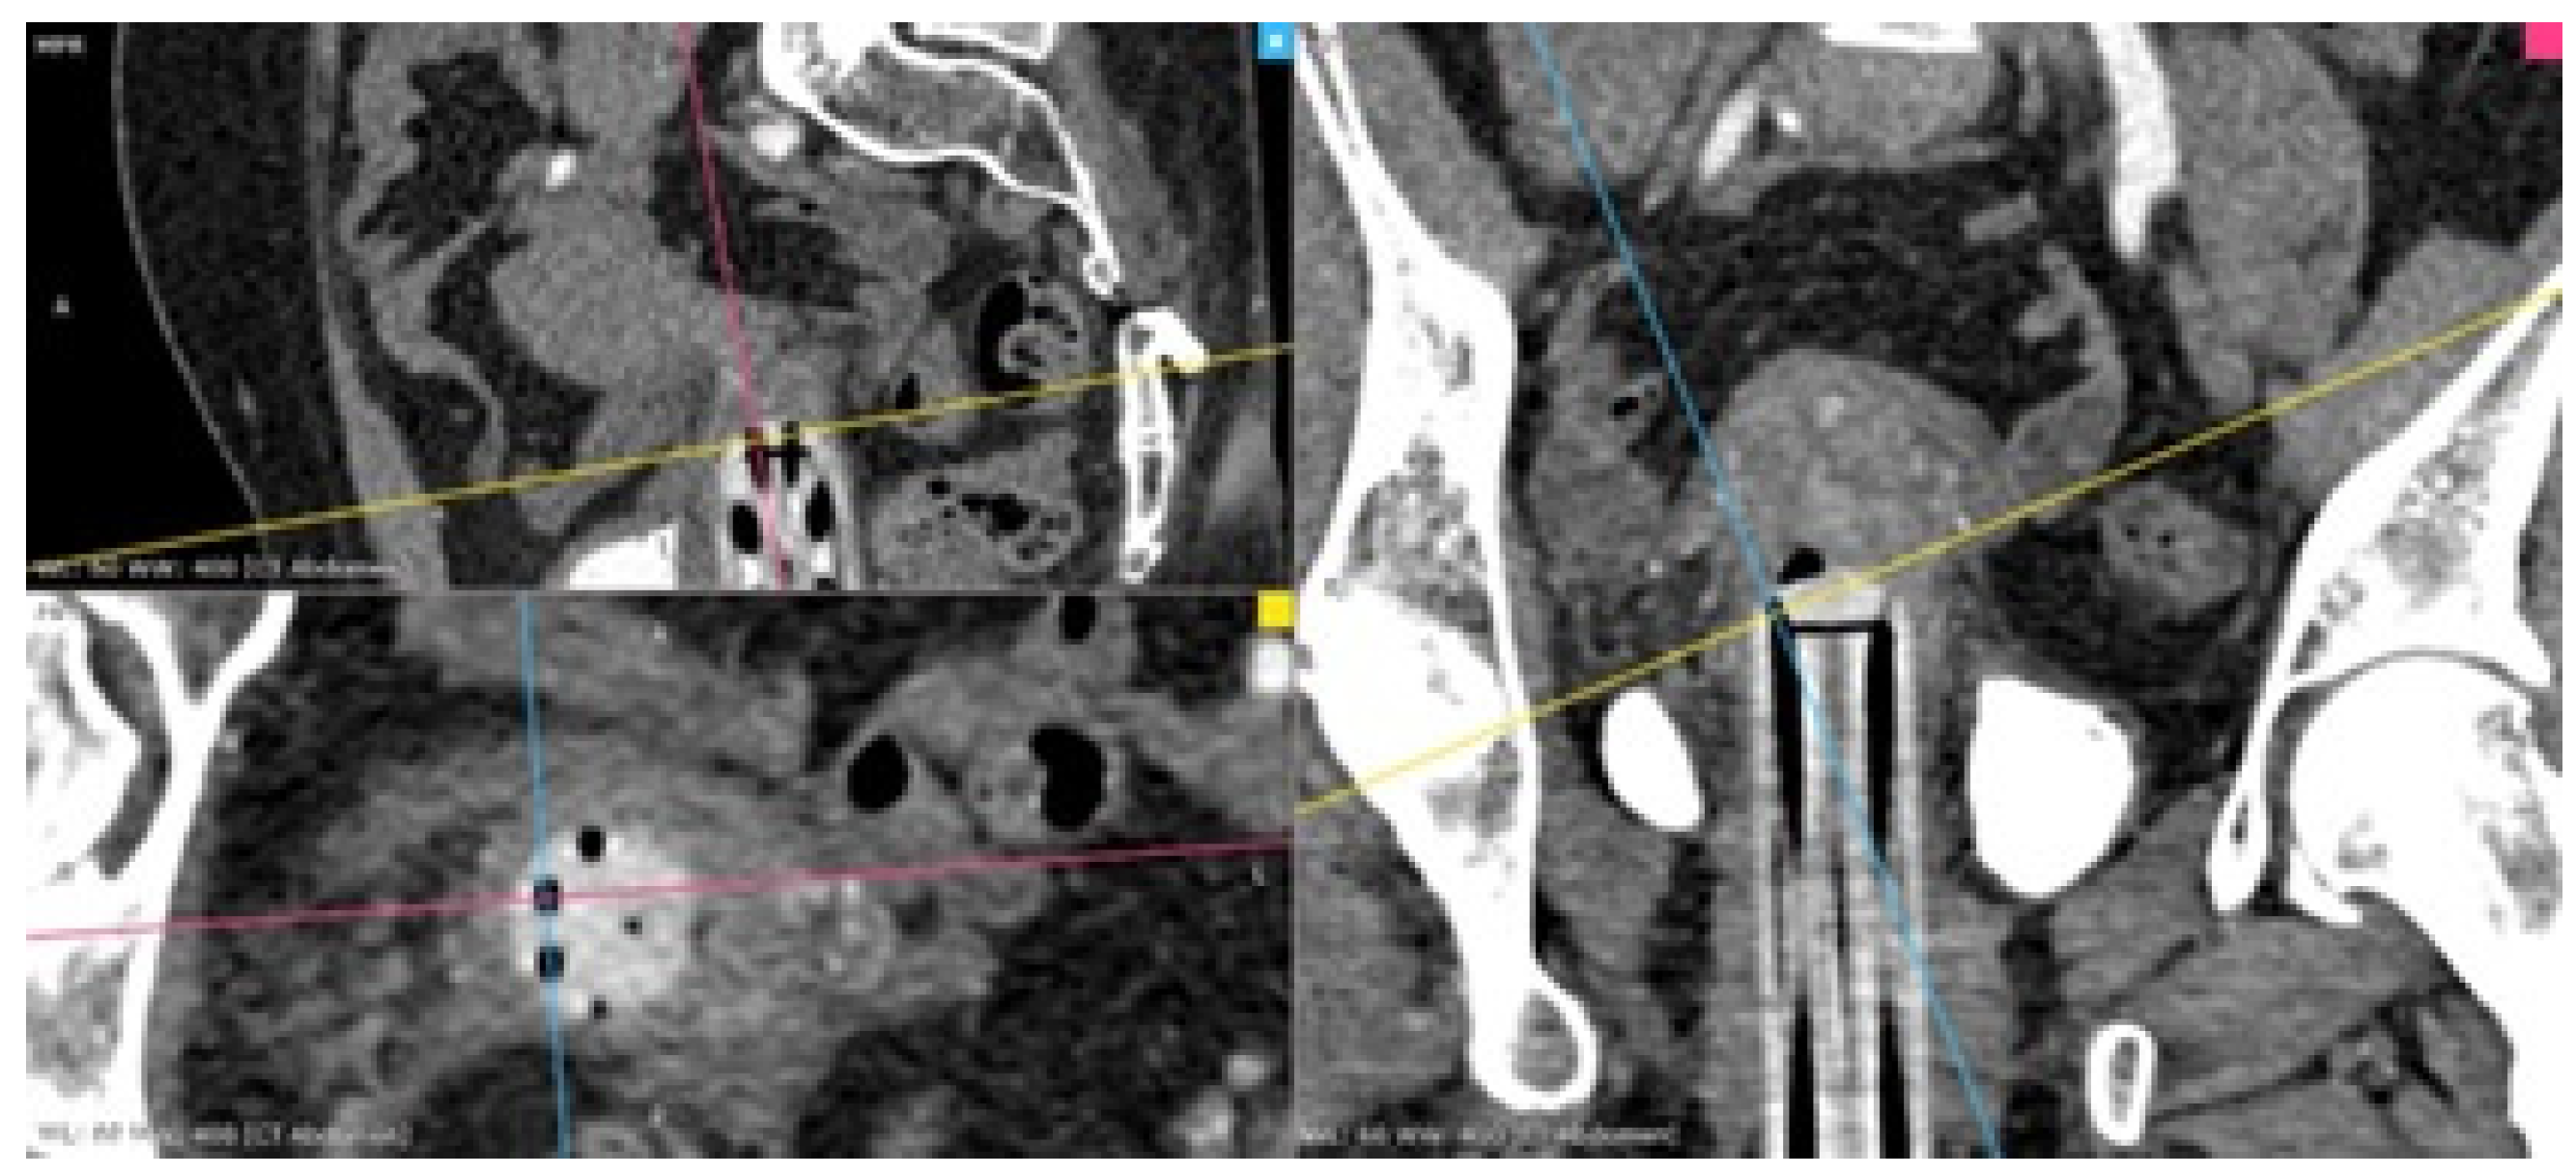

Afterward, the CTAG images are reviewed on a dedicated workstation by a brachytherapy medical physicist and a radiologist with the purpose of identifying the anatomical structures along the needle’s paths. Multiplanar reconstructions (MPR) are created along the last 5 mm of each needle channel axis, to account for the distal angles of the three types of applicators (Figure 1). We measured the distance between the upper orifice of each channel and organs-at-risk predisposed to puncture complications, such as the uterine arteries, ureters, urinary bladder, rectum and bowel (Figure 2). Based on these measurements, optimal needle insertion depth is calculated, while keeping a safety distance of 5 mm from the organs previously mentioned.

Figure 2. Distances between the internal channel orifices of an Aarhus ring device and (a) the uterine artery, (b) the sigmoid colon, (c) the bladder. (S-sagittal).